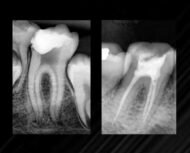

Endosealer Plus es un sellador de conductos radiculares con un sistema de reacción de resina epoxi-amina con propiedades físicas y químicas excepcionales. Presenta un sistema de homogeneización en puntas auto-mezcladoras, permitiendo la aplicación directa en el conducto radicular, ahorrando tiempo y material. Posee excelente radiopacidad, favoreciendo la observación del campo clínico en imágenes radiográficas.